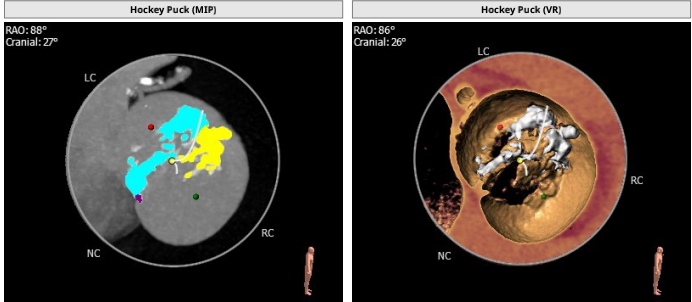

主动脉根部解剖: